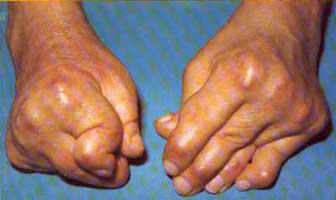

严重畸形的RA

严重畸形,功能丧失的RA